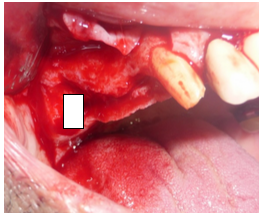

A técnica de incisão de descolamento de retalho para a utilização do aparelho piezoelétrico não difere da técnica convencional ditada do Tatum (figura 3).